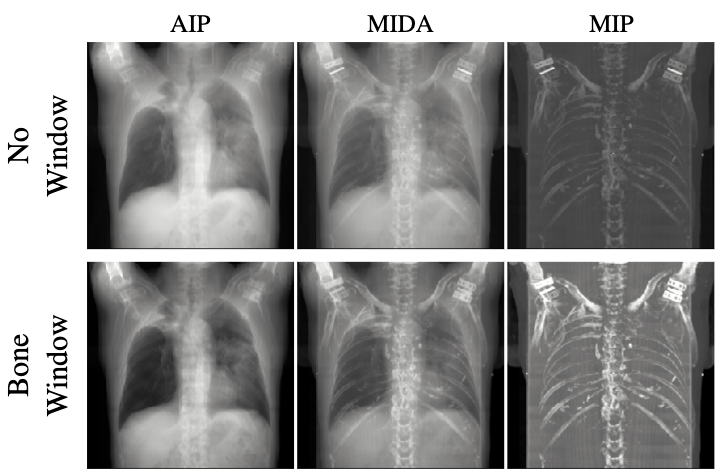

The most direct way to transform a typical 3D CT volume data to a 2D image is to average the intensity (ray accumulation) along particular directions (view direction) to generate such an X-ray-like image. This approach gives us a brief sense of how overall the 3D CT data looks like in the context of projection, but it does not look similar to the real X-ray image that is commonly taken, in terms of contrast or intensity, even with common pre-windowing setups of CT data (see Fig. 1). It can be explained that this averaging intensity projection (AIP) does not fully reflect the photon attenuation of heterogeneous absorber (CT data) measuring in the Hounsfield Unit (HU) scale. Several techniques such as MIDA [2] combines a linear lookup table (intensity versus opacity) and non-linear ones such as Maximum-Intensity Projection (MIP) to promote better certain material visualization.